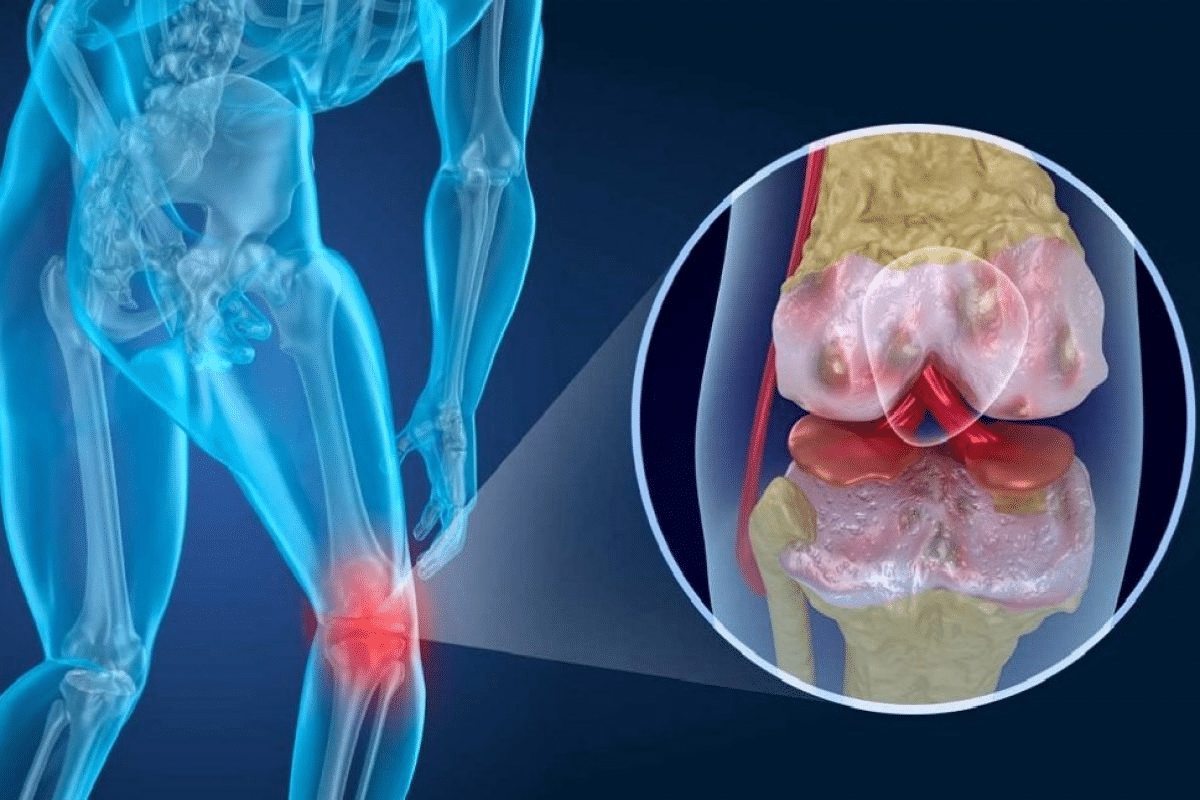

The Autoimmune Response in Joints

The start of RA involves an autoimmune response that mainly hits the synovium, the joint lining. This leads to swelling, making the synovium thicker and causing damage to the cartilage and bone around it.

The immune system in RA creates inflammatory cytokines and activates immune cells like T cells and B cells. These cells are vital in keeping the inflammation and joint harm going in RA.

Inflammation’s Impact on Bone and Cartilage

In Stage 3 RA, inflammation damages cartilage and bone a lot. This damage leads to pain, swelling, and less mobility. It also makes the body produce harmful substances that worsen the condition.

• Cartilage degradation, leading to joint space narrowing

• Bone erosion, causing structural damage to joints

• Formation of bone spurs or osteophytes